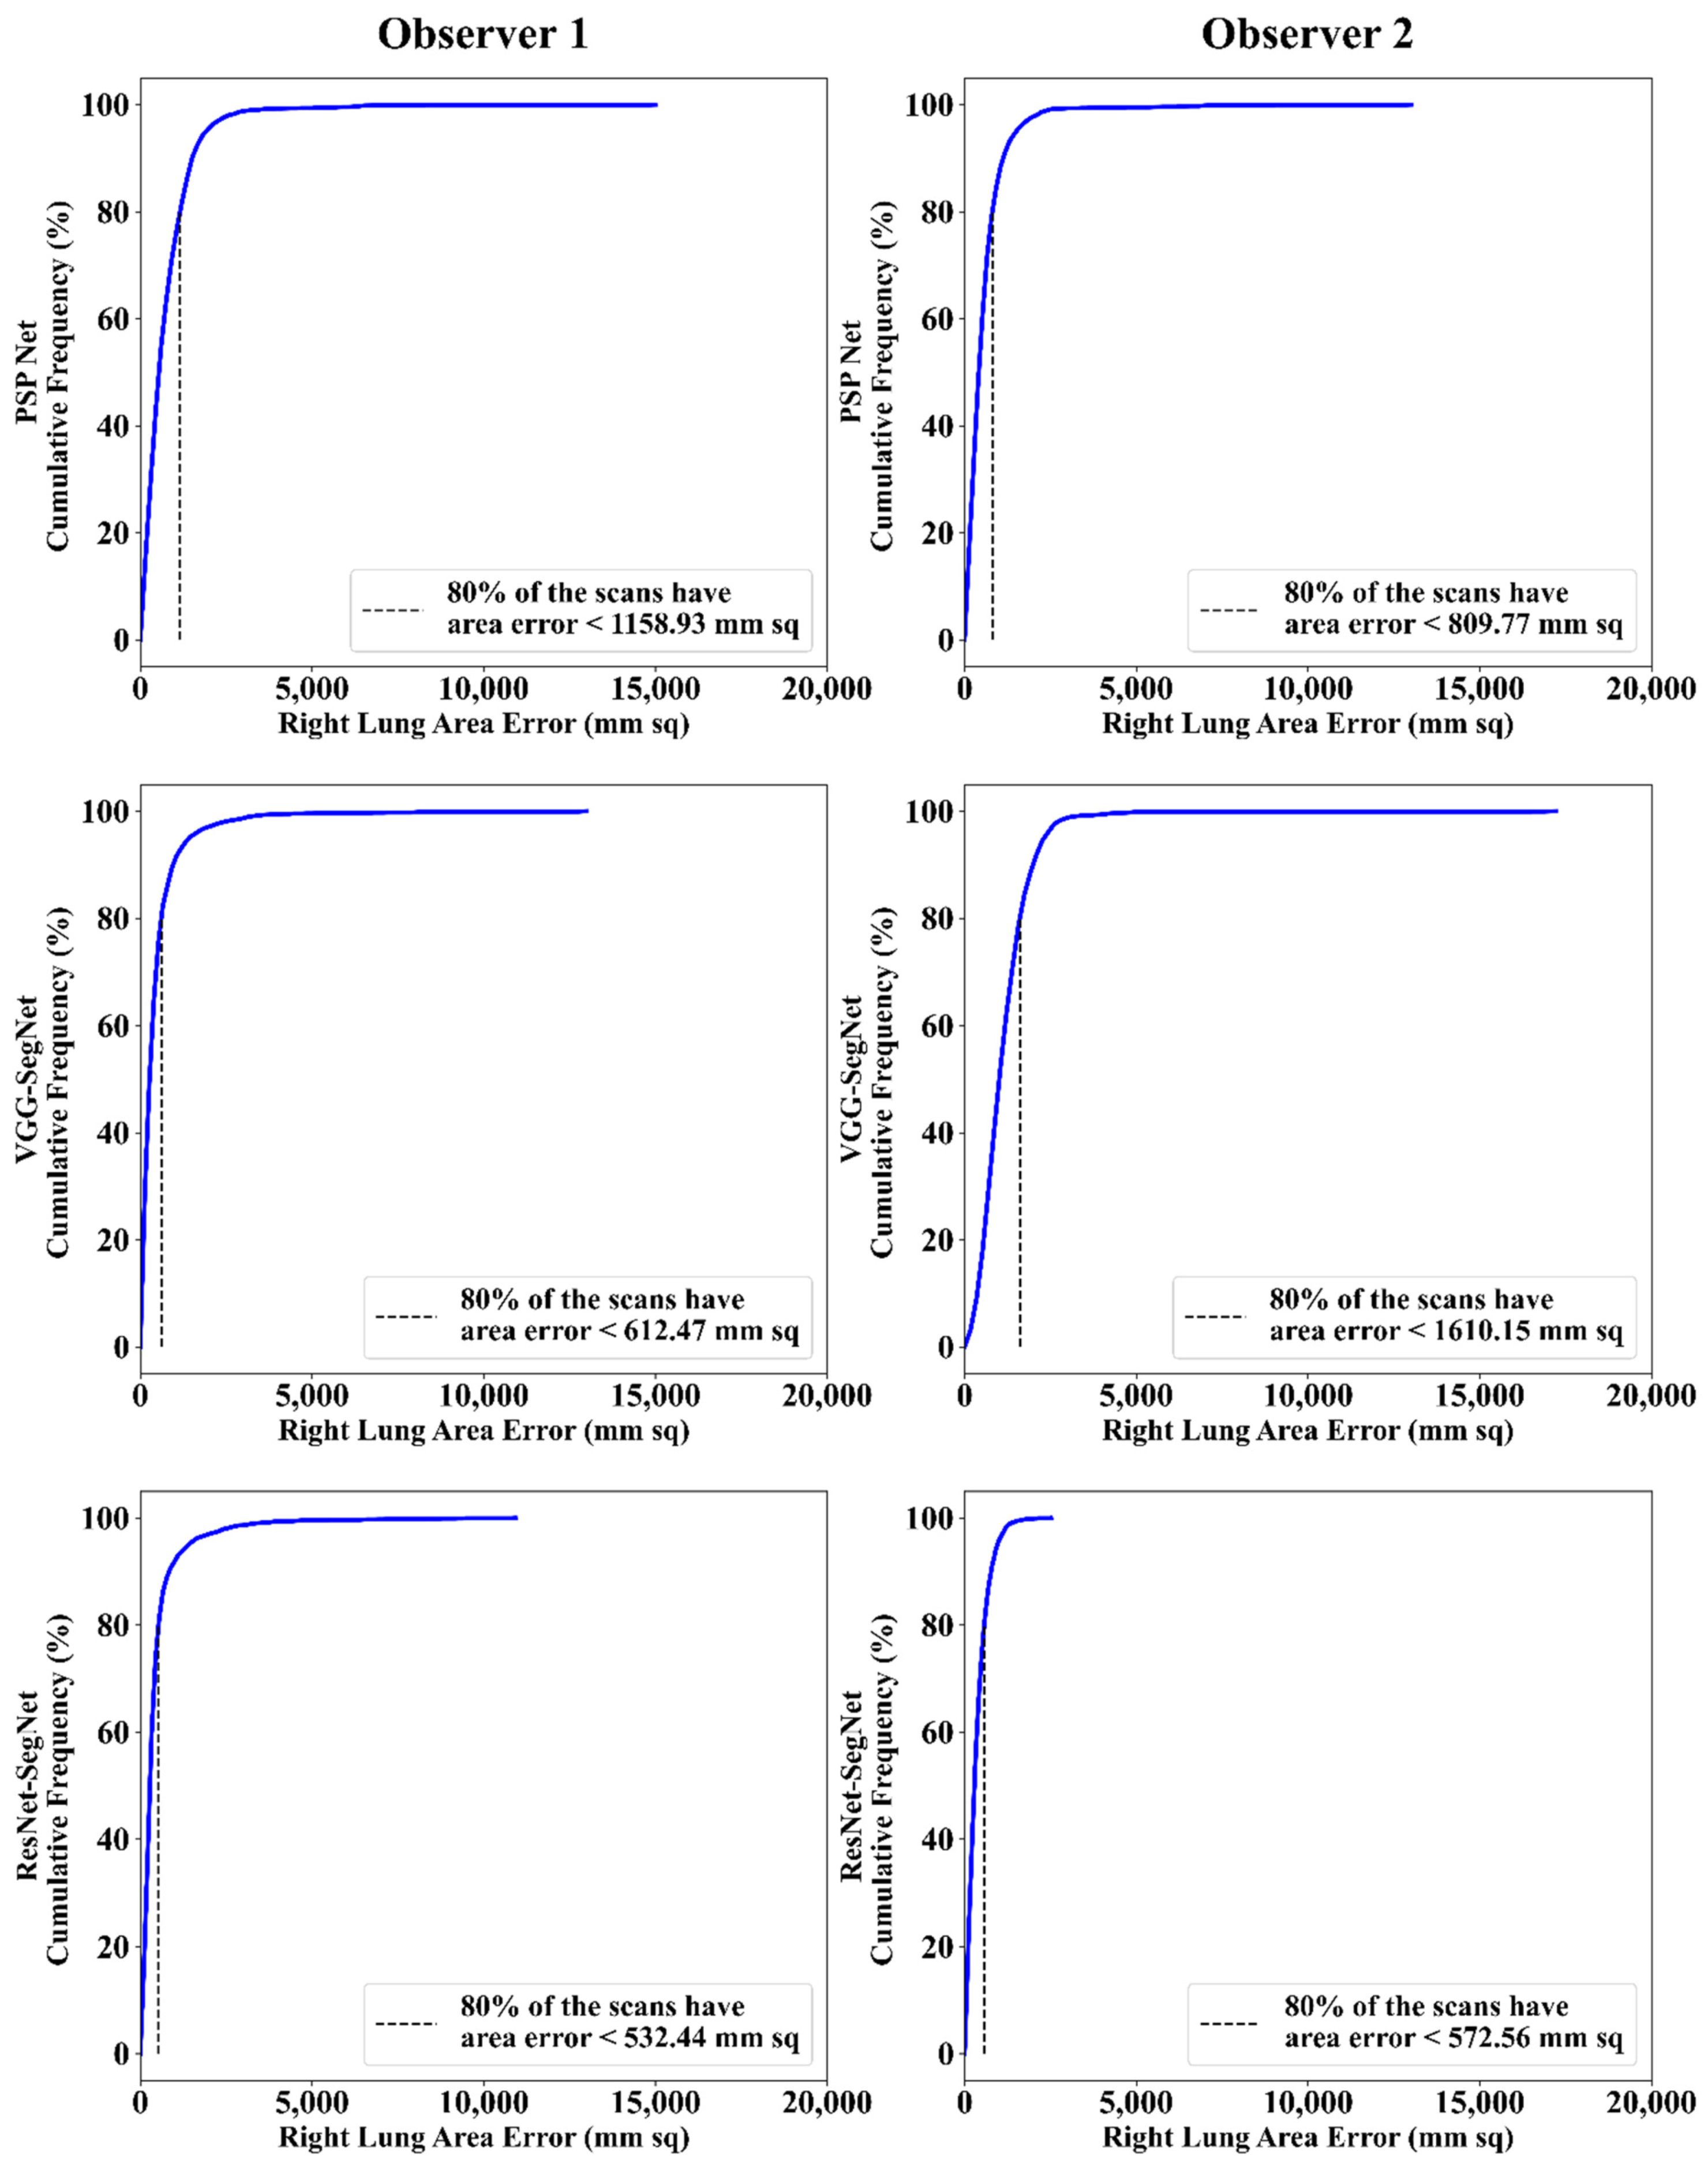

Cumulative Frequency Plot for Lung Area Error